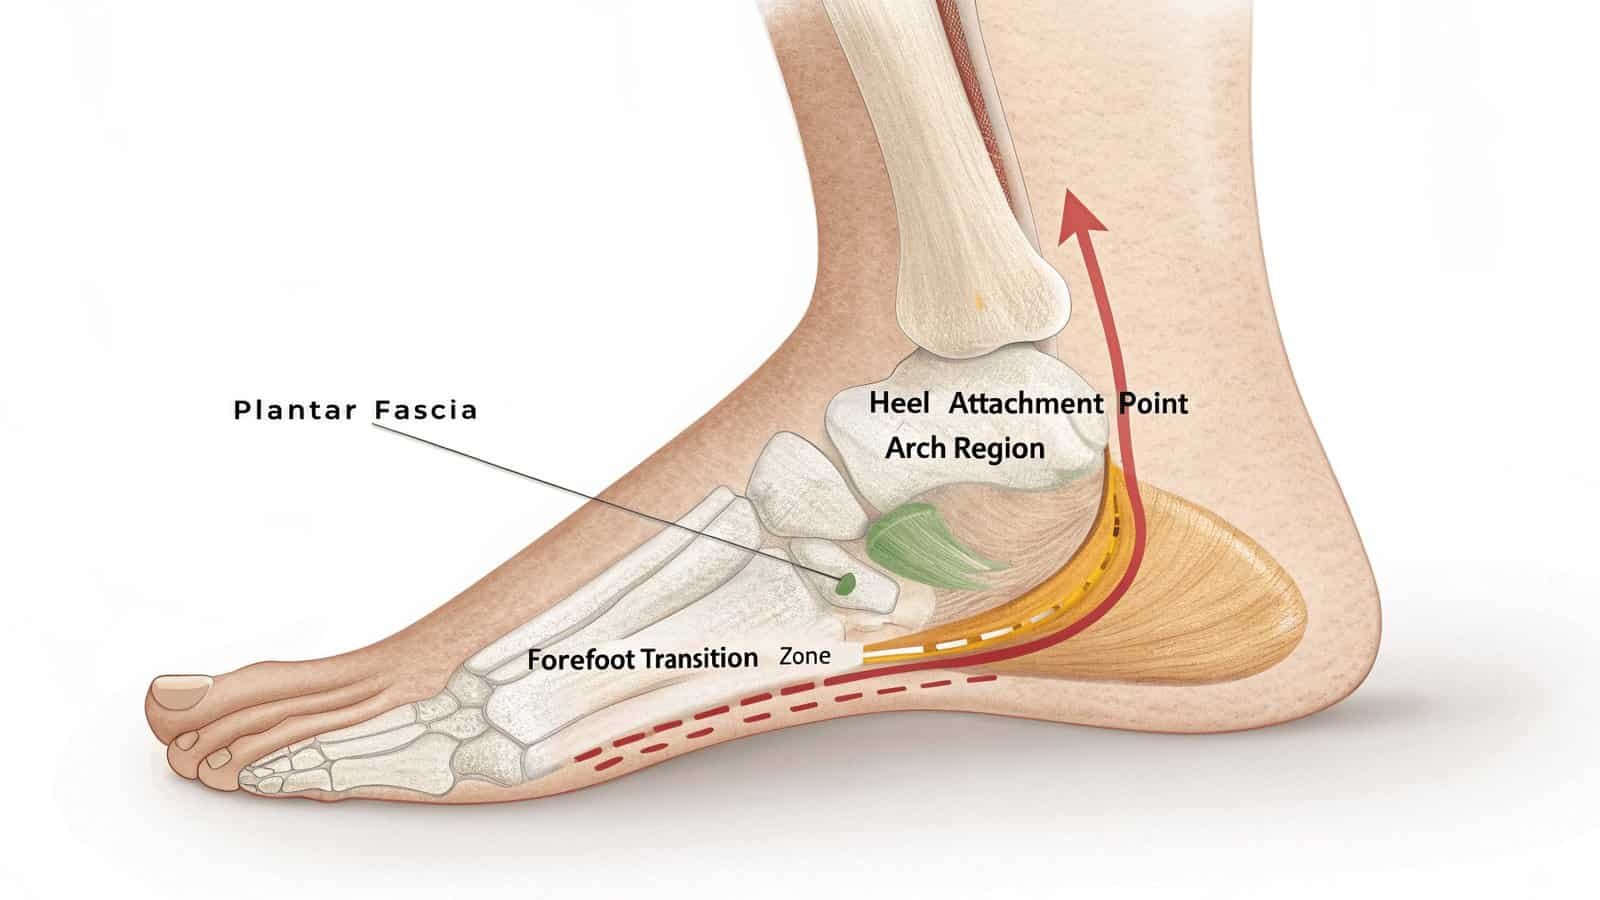

The plantar fascia absorbs shock during movement. Overuse, poor mechanics, or sudden increases in activity strain this tissue, causing microtears and inflammation at its weakest points.

Critical Stress Zones

The plantar fascia suffers most at these key locations:

1. Heel Attachment Point

- Bears maximum tension during push-off

- Poor cushioning increases impact forces

- Our therapy gun’s rapid pulses (4000-6500 RPM) break pain cycles here

2. Arch Region

- Collapsed arches overstretch the fascia

- High-frequency vibrations improve tissue elasticity

- 3D motion stimulates blood flow for healing

3. Forefoot Transition Zone

- Where fascia fibers fan out

- Requires precise 2mm amplitude treatment

- Horizontal+vertical vibrations address multidirectional stiffness